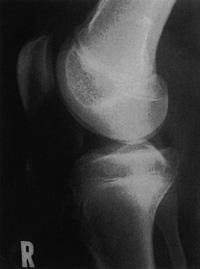

12歳の女児。ミニバスケットボールの練習を始めてから、右膝のやや遠位部に疼痛と腫脹とが出現したため来院した。症状は運動後に悪化し、安静で軽快する。エックス線写真を示す。認められるのはどれか。

1

大腿骨遠位骨幹端部の骨膜反応

2

大腿骨顆部の骨硬化

3

膝蓋骨の骨棘形成

4

脛骨顆間隆起の尖鋭化

5

脛骨粗面部骨端の不整

12歳の女児。ミニバスケットボールの練習を始めてから、右膝のやや遠位部に疼痛と腫脹とが出現したため来院した。症状は運動後に悪化し、安静で軽快する。エックス線写真を示す。この患者の理学療法で適切でないのはどれか

膝サポーターの装着

大腿四頭筋のストレッチ

疼痛部のアイスマッサージ

スクワットによる下肢筋力訓練

ハムストリングスのストレッチ